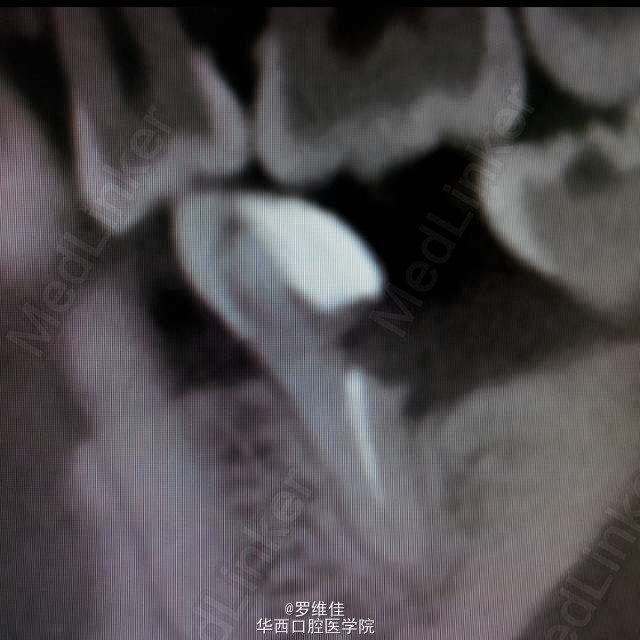

患者,女,29岁,D区的第一恒磨牙(分为近中根和远中根)远中根根管治疗后失败,根尖周有暗影,炎症反应,而近中根完好。原定计划方案:拔除第一恒磨牙,原位种植修复。但患者极其强烈要求保住近中根,只拔除远中根。根据患者极其特殊的要求改变治疗计划为:分根,拔除远中根,远中根原位植入种植体一枚,近中根备牙后进行烤瓷冠修复,目前种植体已植入,冠正在制作中